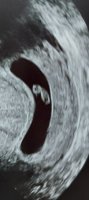

Har TUL privat neste fredag. Krysser fingrene for at jeg får se et bankende hjerte da!

Fikk høre hjertet også- veldig deilig!